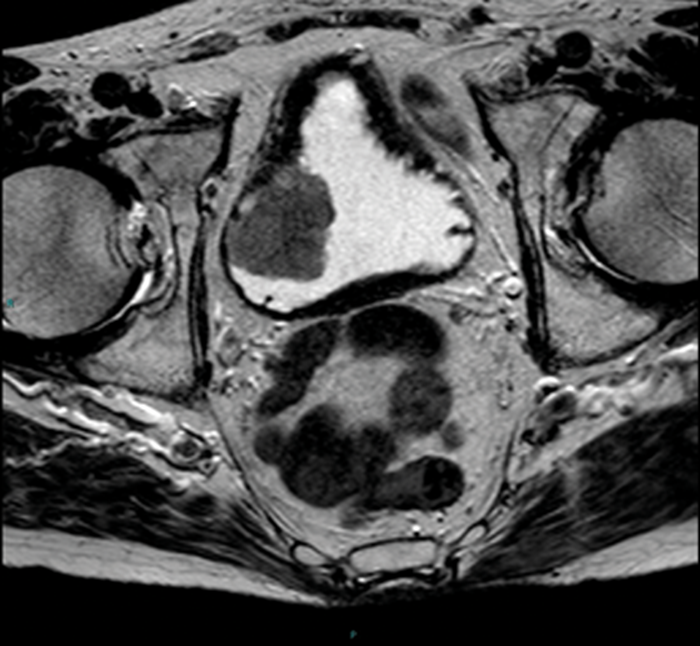

Enhanced MRI showing a bladder tumor at the left wall (arrow). Arrow…

Urinary Bladder Cancer: Role of MR Imaging | RadioGraphics

Bladder carcinoma MRI | Urology News

Bladder cancer MRI – wikidoc

mpMRI of a male patient with stage T1 high-grade bladder cancer 3 …